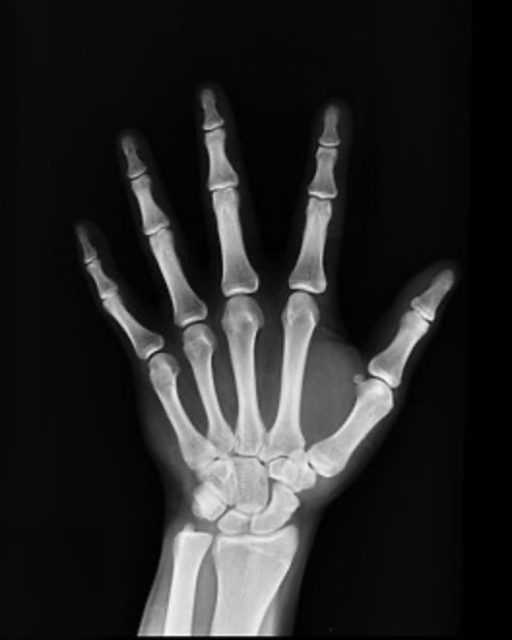

これが子どもの手のレントゲン写真です。

そして、これが大人

だいぶ違いますよね。

当然、同じようなテクニックを使える訳がないのです!!

子どもは軟部組織が本当に多くて、

関節が出来上がっていないのです。